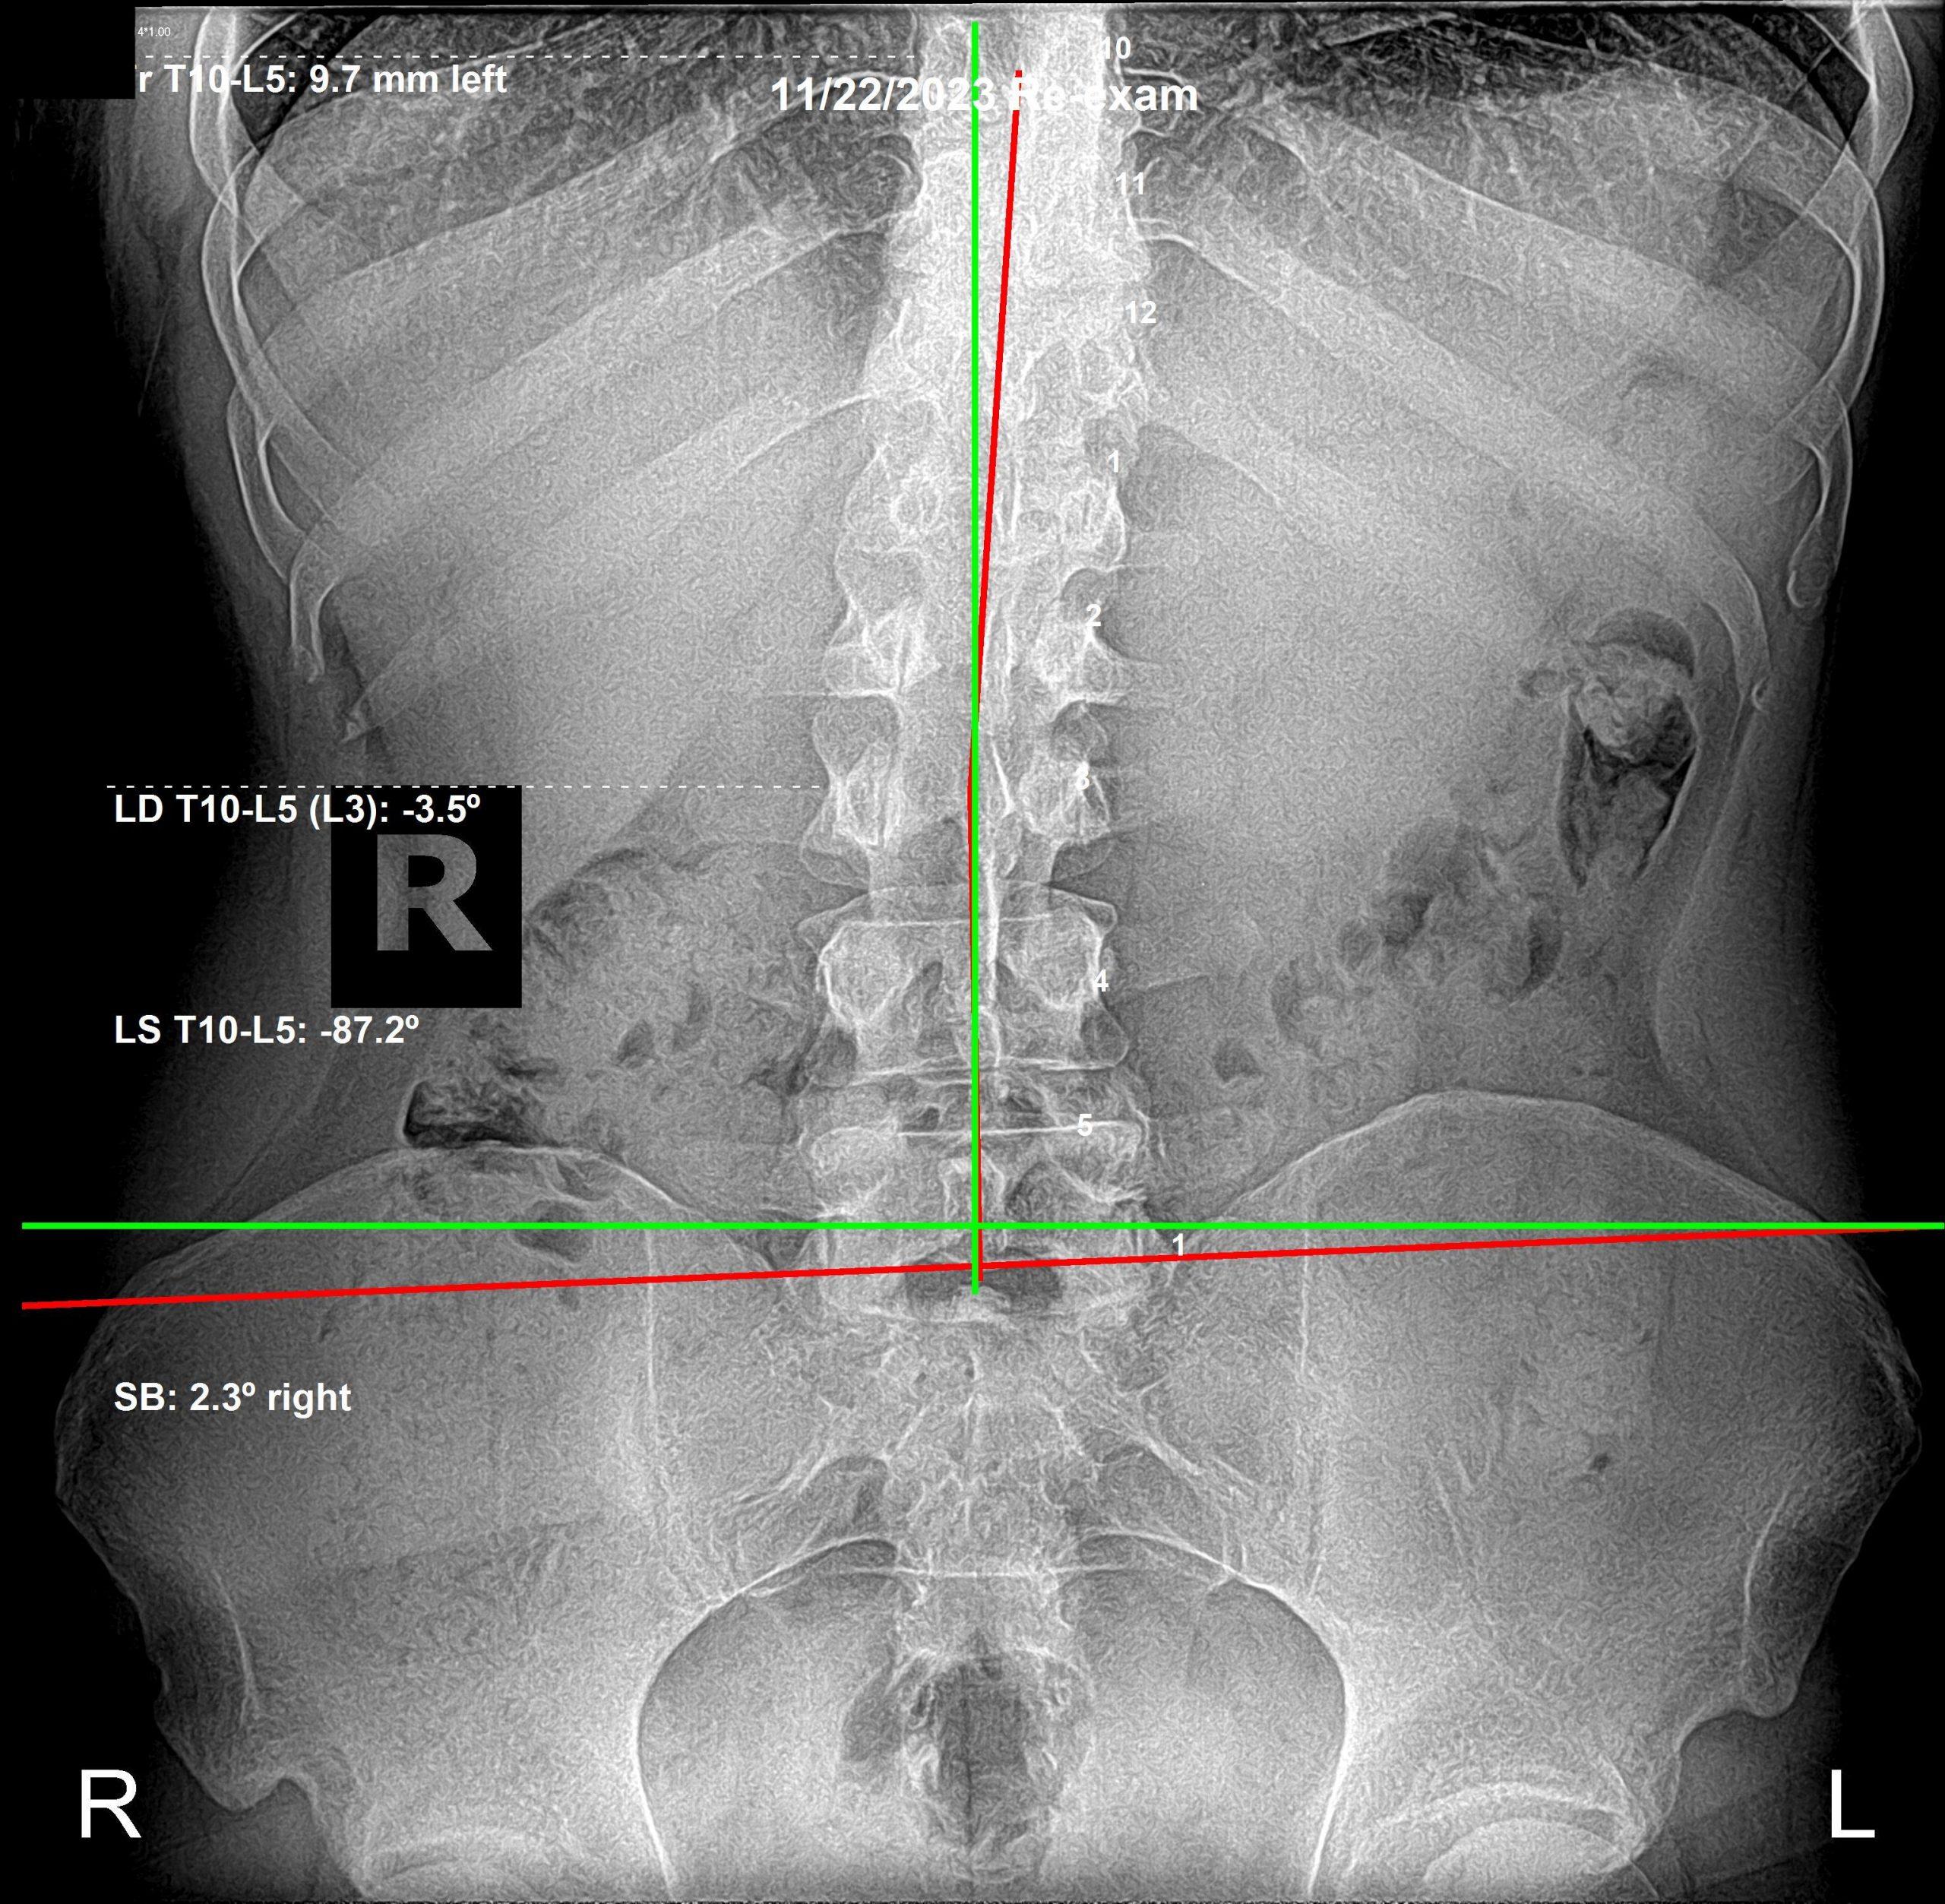

We take initial X-Rays to determine length of corrective care, as well as follow up x-rays to determine continuation of care. Spinal alignment restoration is key to stimulating restoration of function.